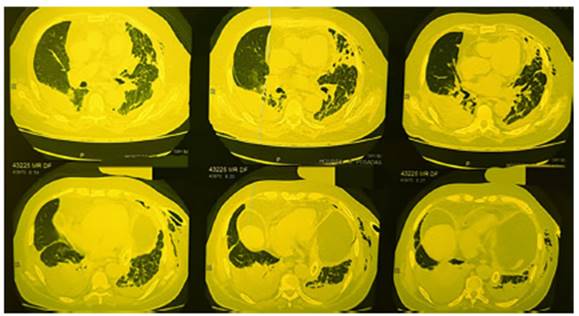

avenamiento pleural. Se inicia empíricamente ampicilina sulbactam (AMS). Tomografía (TC) de tórax: hidroneumotórax izquierdo con tubo de drenaje

pleural, derrame pleural derecho loculado de aspecto

organizado y consolidaciones pulmonares bilaterales a predominio derecho

(Figura 1). Cultivos de líquido pleural izquierdo: Nocardia